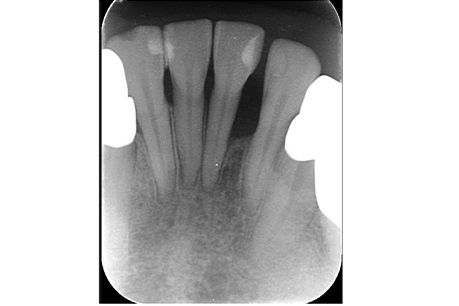

左上6番目

治療の内容:パーフォレーションにより根分岐部病変があり、根尖病変もある症例。歯内歯周病変で歯周病と根尖病変が合併している難治症例。根管治療後分岐部病変が治らなかったため遠心頬側根の歯根切除を行いその後近心頬側根が石灰化しておりそこの根尖病変も治癒が悪かったため歯根端切除も行った。歯周ポケットがなくなり、根尖病変も治癒傾向なため補綴処置を行なった。

治療の期間:8か月

回数:根管治療4回、コア1回、歯根切除1回、抜糸1回、歯根端切除1回、抜糸1回

金額:保険治療

治療のリスク・副作用:術後に歯根破折を起こしたり、清掃不良から歯周病や虫歯を作ることがある。